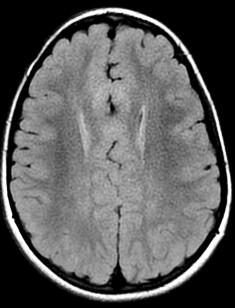

Sweep the Midline:

“Comma shaped Corpus Callosum with abnormal mid body…”

Syntelencephaly: Midline CC “lack of cleavage”

Middle Interhemispheric “MIH” Variant of Holoprosencephaly

Azygous ACA

Polymicrogyria PMG

Cortical dysplasias

GM heterotopia

Absent septum pellucidi